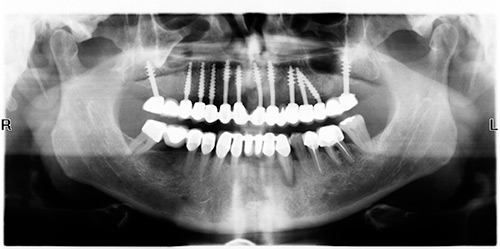

Ho consultato tramite internet lo studio Nemess-Dent in Szombathely in (Ungheria) situato a 30 chilometri dal confine con l’Austria, raggiungibile da Vienna o Bratislava. A priori, ero molto scettico, per quello che mi veniva prospetto, effettuare n. 10 impianti monofase sulla parte superiore, in poco tempo ed a costi accessibili. Non avevo sentito parlare di questo tipo di sistema. Perciò, nel mese di Maggio 2011 ho fissato l’appuntamento e mi sono recato presso lo studio Nemess-Dent per un controllo, il giorno seguente, accompagnato dall’interprete, mi sono recato nello studio dentistico, a me riservato, dove l’impiantologo, effettuando le procedure di rito, mettendomi a mio aggio, eseguendo un ortopanoramica ed accertatosi de tipo di impianti da posizione in base alla mia composizione ossea, ha proceduto all’estrazione dei denti ed al fissaggio n. 10 impianti monofase in poco più di tre ore. Successivamente, a fine dell’intervento, venivo accompagnato in albergo con i medicinali da prendere ed il ghiaccio da mettere sulle guance. Nei giorni seguenti venivo contatto dal sig. Nemess e dall’interprete se necessitavo di qualche cosa. Dopo tre giorni di guarigione, ritornavo allo studio dove mi veniva fissata una protesi in resina da tenere per sei mesi in attesa di guarigione. Nei due giorni successivi ho effettuato altre visite per vedere lo stato delle gengive e degli impianti fissati.

Trascorsi sei mesi di guarigione, ritornavo a Szombathely, dove venivo sottoposto nuovamente a visita; l’impiantologo, procedeva a smontare la protesi, prendeva la nuova l’impronta e nei tre giorni successivi mi fissava la stessa composta da n. 14 elementi in ceramica.

Il costo totale comprendente: estrazione dei denti, inserimento di n. 10 impianti, costruzione di del ponte di n. 14 elementi in ceramica è stato esiguo, di trasporto da e per l’aeroporto, meno della metà dei prezzi praticati dai dentisti in Italia. Mi è stata rilasciata la garanzia del lavoro eseguito e la fattura dell’importo versato.